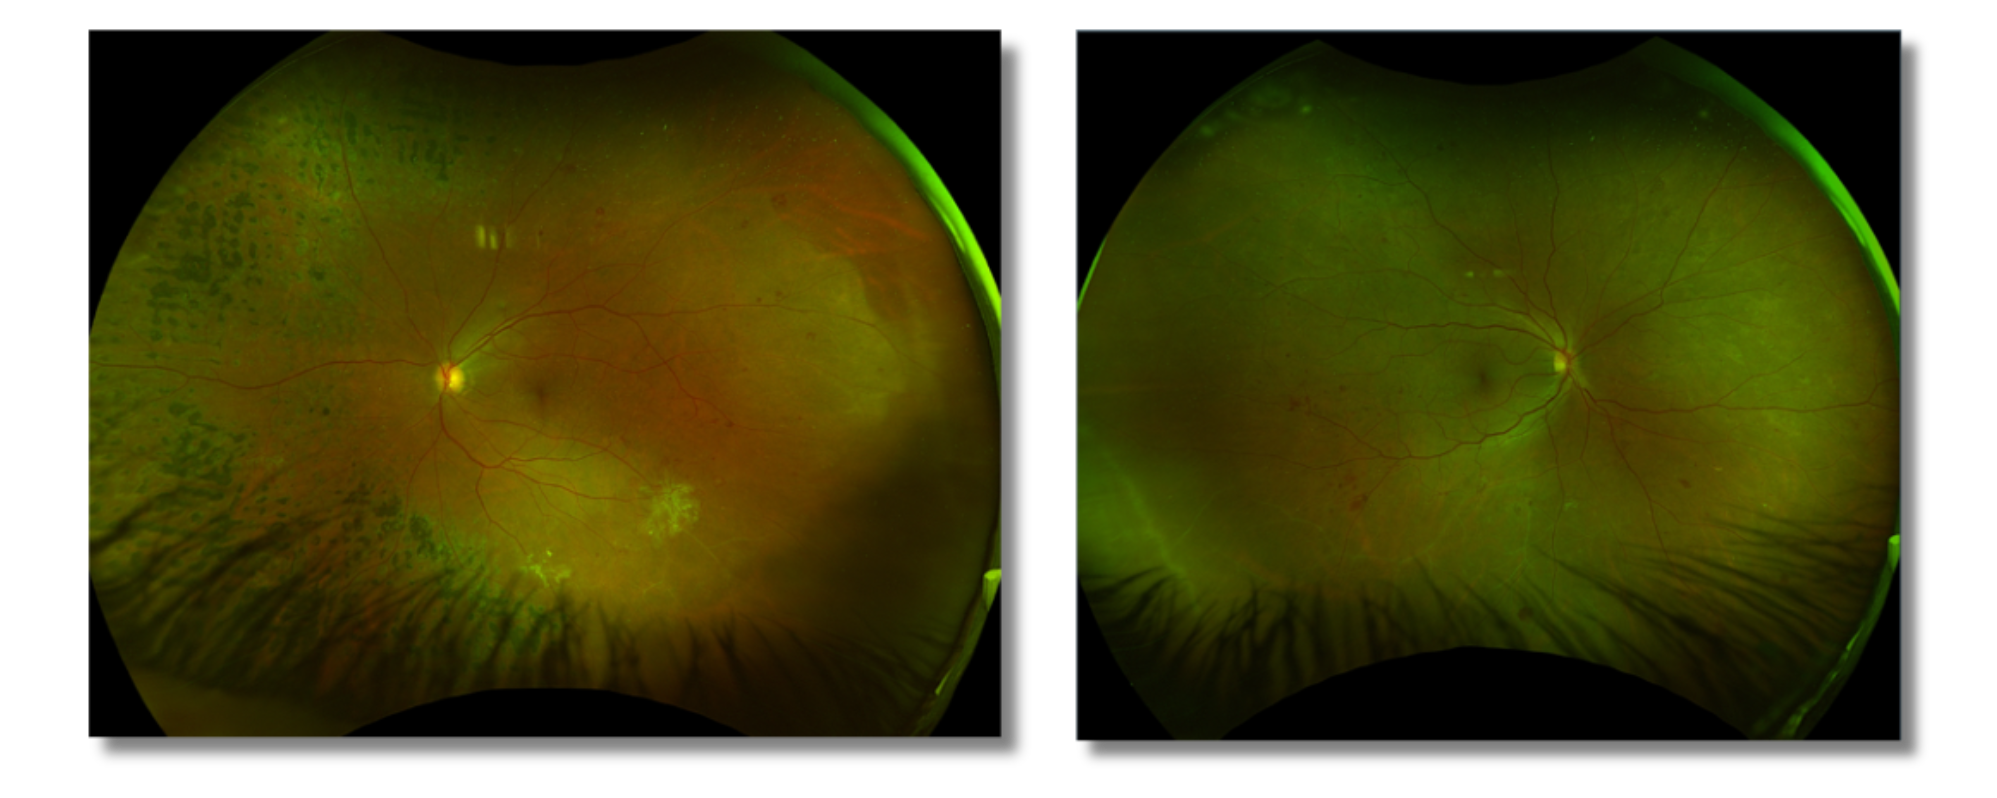

Fundus imaging findings (Figure 2) suggested the need for peripheral laser treatment; however, the signs were mild, and the patient expressed concerns about potential peripheral vision loss associated with PRP. As a result, a RETeval® ERG was requested to evaluate retinal function and help determine the risk of disease progression.

Figure 2: Fundus Images